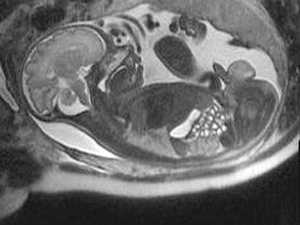

Под диафрагмой справа визуализировалось гиперэхогенное опухолевидное образование несколько неоднородной солидной структуры, с четкими ровными контурами, размером 50x38x35 мм. К нижнему полюсу данного образования прилежала правая почка, имеющая нормальные размеры, форму и структуру. Нижняя полая вена была смещена кпереди и влево. Обращала на себя внимание выраженная гепатомегалия, причем структура печени не была однородной. Она содержала множественные гиперэхогенные включения размерами до 17 мм, окруженные тонким гипоэхогенным периферическим ободком. Цветовое допплеровское картирование(ЦДК) демонстрировало интенсивную периферическую васкуляризацию опухоли (рис. 1-3).

Рис. 1. Нейробластома правого надпочечника плода. Беременность 31 нед 4 дня.